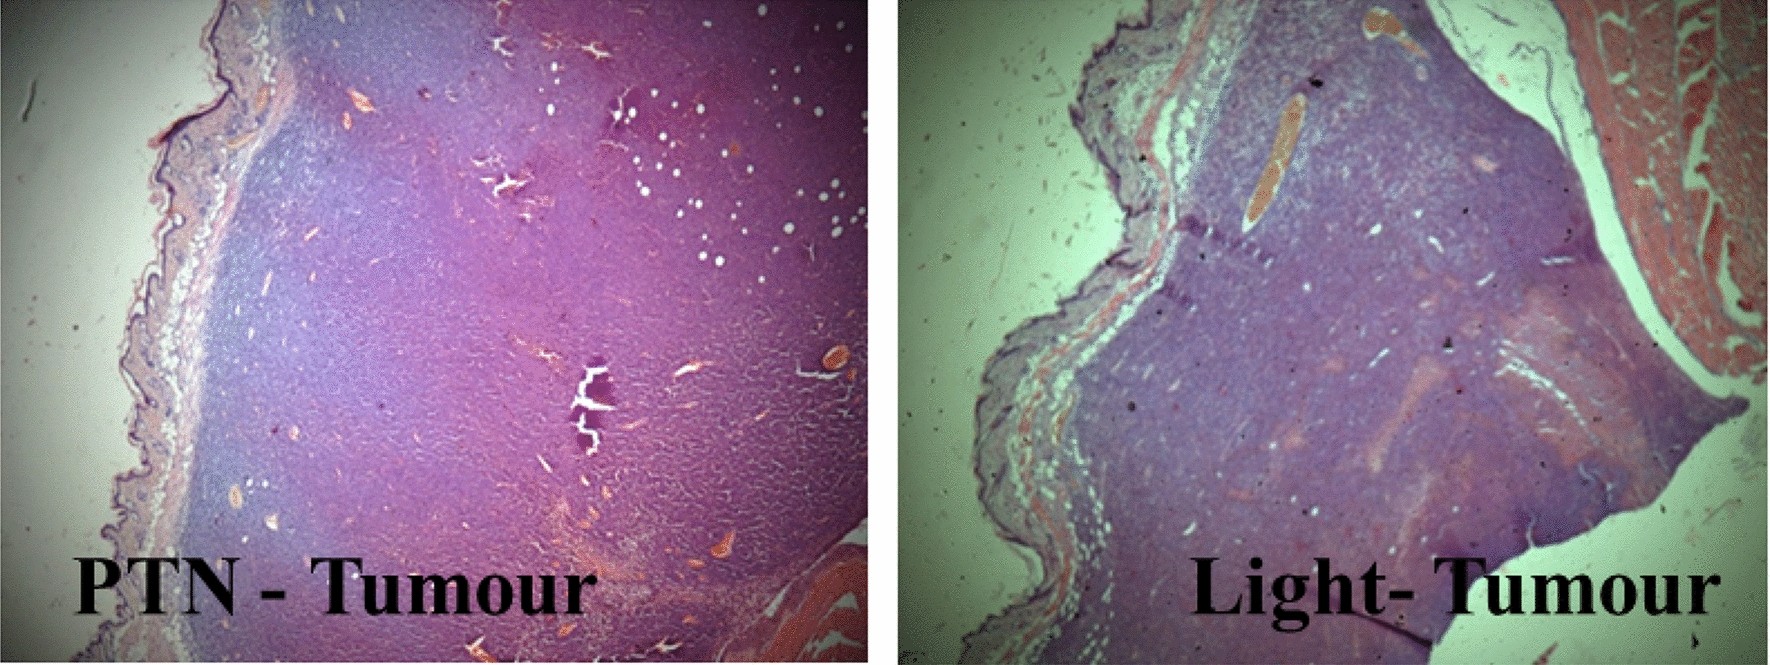

Figure 9

Control tumours treated with PTN or light alone. Tumours treated twice with PTN and non-illuminated (PTN-Tumour) or illuminated twice previous application of vehicle (Light-Tumour); mice were sacrificed and tissues excised 24 h after the last dose. Sections were photographed using the × 4 objective.